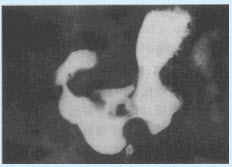

女,9岁,右髋部疼痛、跛行半年,无发热。结合骨盆平片,最可能的诊断为()

A:右髋关节结核

B:右髋关节化脓性关节炎

C:右股骨骨骺骨结核

D:右髋类风湿性关节炎

E:右股骨头骨骺缺血坏死